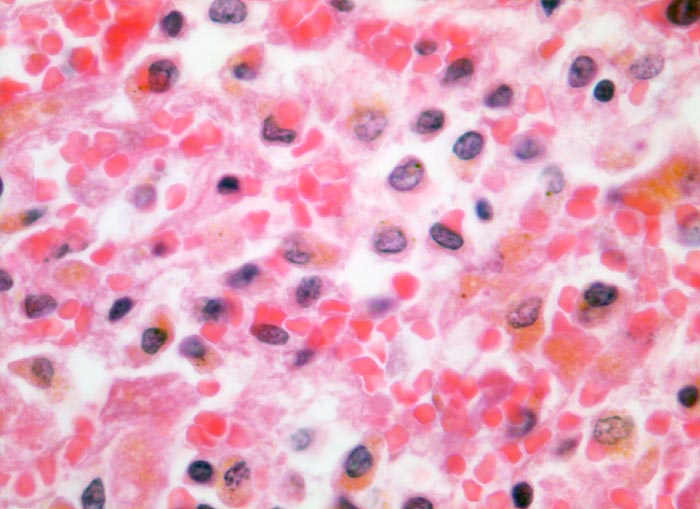

Einleitung

Linksherzversagen oder ein Schockzustand können zu einer hepatischen Minderperfusion mit ischämischen Koagulationsnekrosen der perivenulären Hepatozyten führen. Die Kombination von Hypoperfusion und retrograder Stauung (Rechtsherzversagen) führt zu zentrilobulären hämorrhagischen Nekrosen. Klinisch führen diese Nekrosen zu einer transienten geringen bis mässigen Erhöhung der Transaminasewerte, gelegentlich auch zu einem leichten Ikterus.

Metastasierendes Kolonkarzinom. Als Todesursache fanden sich nicht ganz frische zentrale und perizentrale Lungenembolien.